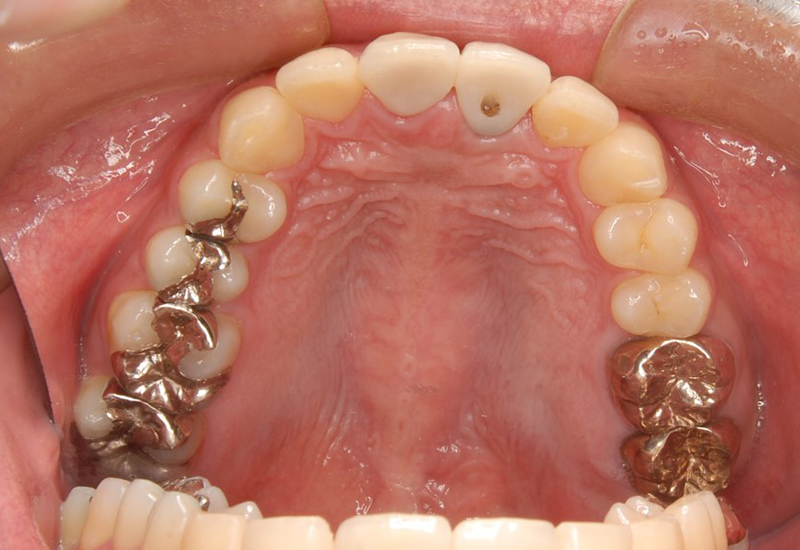

治療経過の写真

手術の様子

術後3ヶ月に仮歯を入れています。

右上1 ジルコニアセット

左上1インプラント補綴セット(ジルコニア)